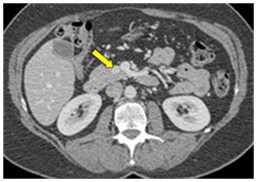

CT scan

CT scan has many advantages since it can be easily performed, is non-invasive and the images are easily interpretable for the surgeon. Insulinoma typically appear as well-defined, rounded, homogeneously masses of the pancreas. Because the majority of insulinoma are usually smaller than 2cm, dynamic CT scan should be performed; the sensitivity of the dynamic CT scan in the detection of insulinoma ranges from 30% to 66%. Dual-phase contrast spiral CT scan is more sensitive than other noninvasive imaging studies. In a group of seven patients with tumors that were biochemically proven but not previously located by ultrasonography, CT scan, or magnetic resonance imaging, six of seven tumors ranging from 6 to 18 mm were detected by dual-phase spiral CT scan. Atypical CT scan imaging of insulinoma includes hypoattenuating masses on enhanced CT or intra-arterial dynamic CT, cystic masses, and calcified masses (Figure 1–3).26–30

Figure 7a CT scan showing an insulinoma (white dot pointed to by yellow arrow) in the body of the pancreas (P with arrows pointing to the body and tail of the pancreas). The stomach (S with green lines up and down) has air (black) and fluid (darker gray) with it (stomach wall at end of lower green line). 42

Figure 7b CT scan showing insulinoma (white dot pointed to by yellow arrow) in junction of head and uncinate portions of pancreas. Just to the right of the insulinoma is the portal vein (white with "tail"–vein from the spleen joining it) carrying blood from intestine and pancreas to liver. 42